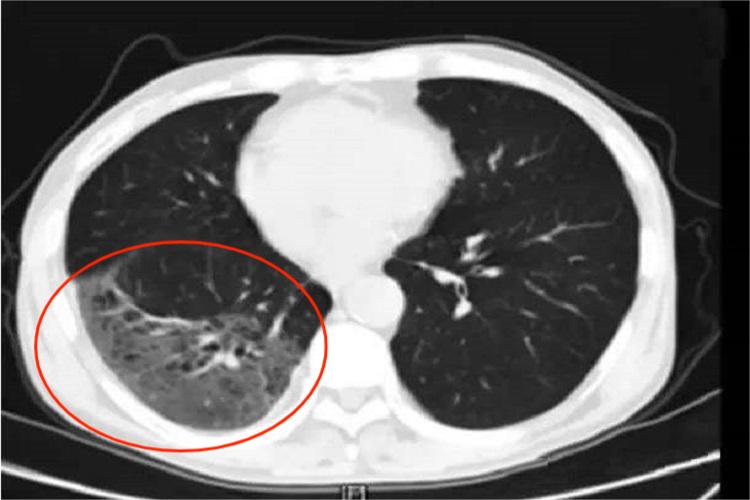

不同病原肺炎的影像学表现

根据X线及病理分类,肺炎分为大叶性肺炎、支气管肺炎和间质性肺炎。X线平片对于肺炎的价值可确定肺内有无病变;可确定病变的部位;可确定病变的范围;了解病变的动态变化;了解有无合并症;...[详细]